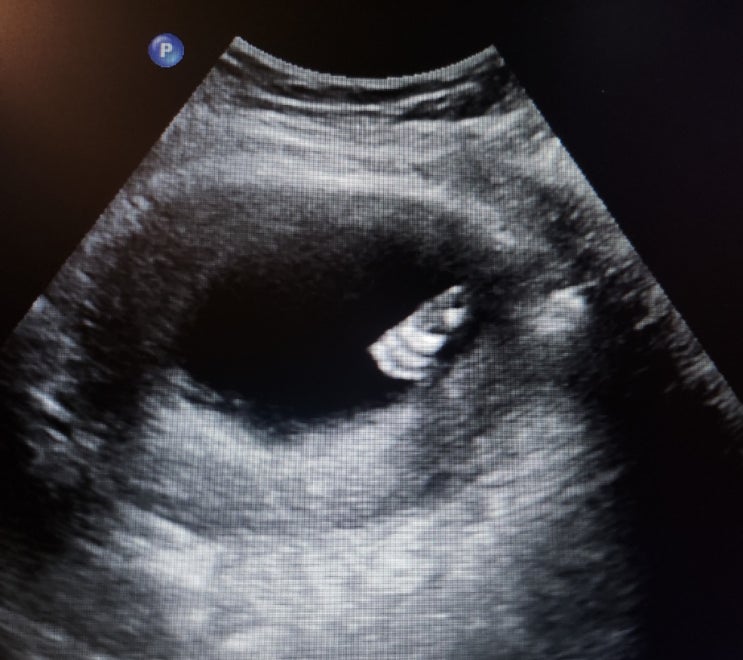

[9주 0일]귀여운 젤리곰 시기/드디어 복부초음파로 봤음.

9주0일 귀여운 젤리곰 시기!! 길게 느껴졌던, 2주 만에 다시 산부인과에 내원했다. 이번에는, 5과 선생님으...